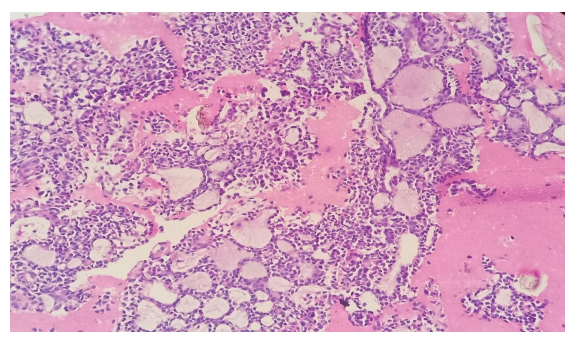

A 38 year old female presented with the complaints of pain and difficulty during swallowing and history of weight loss. Up on examination, a swelling was noted on the left side of her neck, which moved with deglutition. Ultrasound (USG) revealed a well circumscribed hypoechoic nodule measuring 3.2x2.1cm in the left lobe of thyroid with no extrathyroidal extension, however the nodule was compressing the esophagus. Fine needle aspiration was performed on the lesion and stained with Papanicolaou (PAP) stain and May Grunwald Geimsa (MGG) stains. The smears exhibited high cellularity with globoid clusters and three dimensional tissue fragments composed of aggregates of cells with central core of homogenous basement membrane material with cells having basaloid morphology and scant cytoplasm (Figure 2). MGG smears highlighted pink/ magenta amorphous basement membrane hyaline globules in the clusters of tumor cells (Figure 3). Cell block preparation of fine needle aspiration showed cribriform pattern of tumor cells with hyaline globules (Figure 4). Immunocytochemistry conducted on cell block shows TTF-1 positivity in normal thyroid follicles and negative staining in tumor cell clusters. CD117 and synaptophysin were inconclusive on cell block, but based on morphology this case was reported as adenoid cystic carcinoma of thyroid. Contrast-enhanced computed tomography (CECT) prior to surgery depicted a well defined heterogeneously enhancing hypodense lesion in the left lobe of thyroid measuring 3.2x2.1x1.7cm with no  additional lesions or abnormalities noted in the adjacent structures like trachea, larynx, oesophagus or upper mediastinum(Figure 1).  The excised left hemi-thyroidectomy specimen was received which showed a grey white solid homogenous lesion measuring 3.5x2.2x2cm reaching till the capsule. No cystic spaces/papillary projections/colloid seen in the lesion grossly. Adjacent thyroid parenchyma was normal. Histopathology sections showed tumor arranged in tubules and cribriform pattern along with hyaline globules suggesting the diagnosis of adenoid cystic carcinoma of thyroid, limited to thyroid without extra thyroid extension (Figure 5). IHC with CD117 showed cytoplasmic positivity in tumor cells further supporting the diagnosis (Figure 6).

Figure 5: H & E section from Left hemithyroidectomy specimen (20x) show well circumscribed tumor with features of adenoid cystic carcinoma, limited to thyroid with adjacent normal thyroid parenchyma (Arrow marks the junction of tumor with normal thyroid parenchyma).